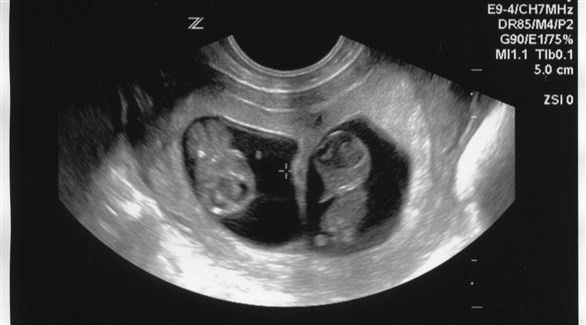

الجريبات: أول علامات الحمل التي يمكن رؤيتها عن طريق الفحوصات هي جريبات الحمل (كيس الحمل)، والتي تبدو بيضاوية الشكل في تصوير الألتراساوند. بعد مرور 4 أسابيع من الحمل يمكن رؤية جريبين (كيسين) إذا كان الحمل بتوأم غير متطابقين. أما التوأم المتطابق فينمو في جريب واحد، ولا يمكن رصدهما قبل الأسبوع الـ5 عن طريق الألتراساوند.